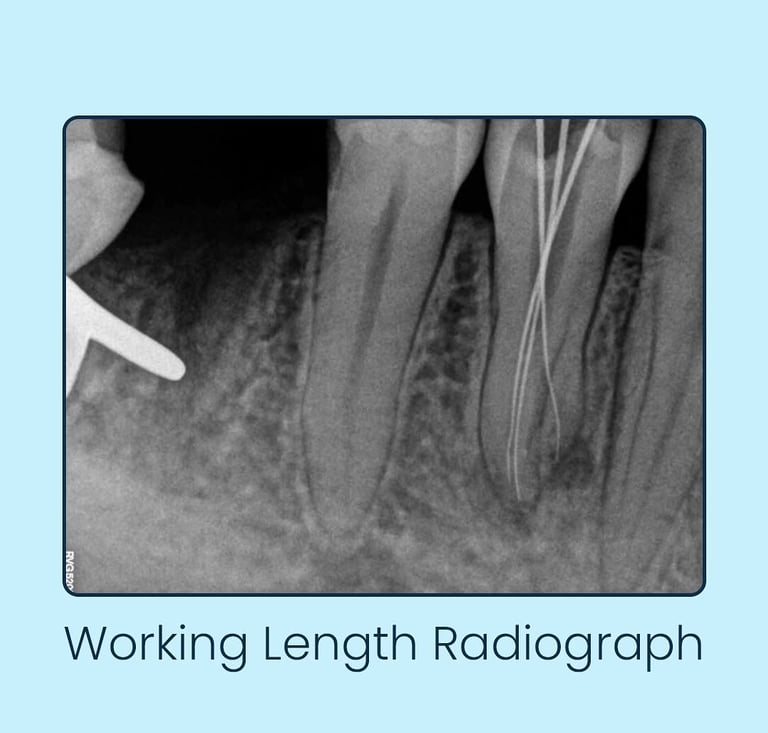

Case Study: A Rare Anatomical Variation in Endodontics

Performed by Dr. Anukrati Srivastava – House of Endodontics, Jaipur